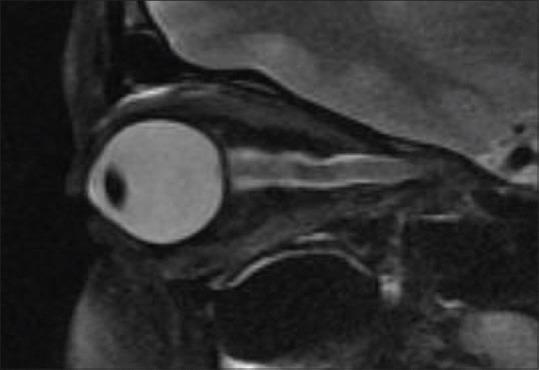

Intracranial hypertension is a syndrome of elevated intracranial pressure that can be primary or secondary. The primary form, now termed idiopathic intracranial hypertension (IIH), was in the past a disease of exclusion and imaging played a limited role of excluding organic causes of raised intracranial pressure. However imaging markers have been described with patients with IIH at the orbit, sella and cerebral venous system. We wish to reiterate the characteristic imaging features of this poorly understood disease and also emphasise that stenting of the transverse sinus in select cases of IIH is an efficacious option.

颅内高压是一种颅内压升高的综合征,可分为原发性或继发性。原发性形式,现称为特发性颅内高压(IIH),过去是一种排除性疾病,影像学在排除颅内压升高的器质性原因方面作用有限。然而,已经描述了IIH患者在眼眶、蝶鞍和脑静脉系统的影像学标志物。我们希望重申这种了解甚少的疾病的特征性影像学表现,并强调在某些IIH病例中对横窦进行支架置入是一种有效的选择。